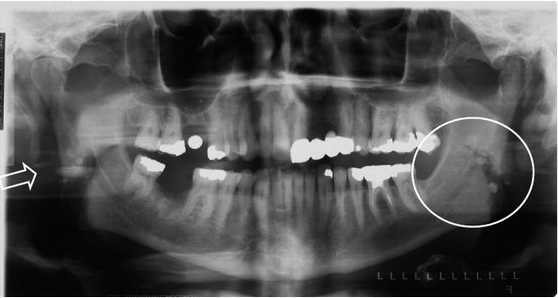

8. What condition can be seen in the following X ray? (the arrow)

9. What condition can be seen in the following X ray? (the circle)